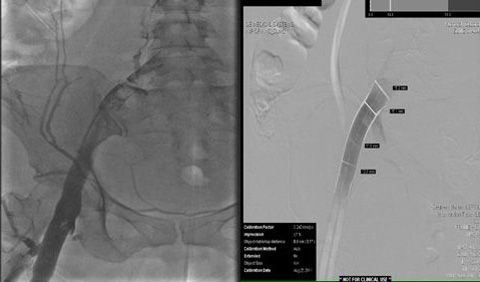

Because of her young age and presentation of acute-onset DVT with extensive clot burden, transcatheter thrombolysis was performed with successful removal of extensive clots in the popliteal, superficial femoral, femoral, and external iliac veins. Anticoagulation therapy was initiated with unfractionated heparin.

Figure 1

Residual thrombus (Figure 1) was noted in the origin of the left common iliac vein shortly after the procedure and required extensive catheter-directed infusion of tissue plasminogen activator. The following day additional mechanical thrombolysis was performed and the patient underwent post-procedure evaluation with intravascular ultrasound. A persistent round filling defect was noted at the inferior vena cava bifurcation with near complete occlusion of the right common iliac vein. There was progressive recurrence of thrombus in the left iliac venous system (Figure 2) and involvement of the right lower extremity, where a new clot was noted.